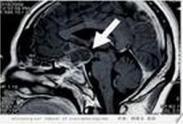

• 空鞍綜合征

628健康網為您分享有關空鞍綜合征的癥狀,空鞍綜合征的治療方法,空鞍綜合征的預防知識,空鞍綜合征的癥狀圖片,空鞍綜合征...